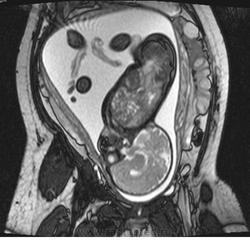

Иниэнцефалия представляет собой летальный сложный порок развития, возникающий в результате несмыкания нервной трубки. Для него характерно отсутствие части или всей затылочной кости со значительным расширением большого затылочного отверстия, в результате чего большая часть головного мозга располагается в области задней черепной ямки и частично в верхнем отделе позвоночного канала. В связи с этими анатомическими нарушениями верхняя часть позвоночника укорачивается и расщепляется и образуются энцефалоцеле и/или spina bifida. Характерным признаком иниэнцефалии является патологическое усиление лордоза. Иниэнцефалия относится к редким аномалиям с неустановленной этиологией, хотя сообщалось о возможном тератогенном генезе порока, чаще всего на фоне приема лекарственных препаратов в ранние сроки беременности (винбластин, стрептонигрин, трипаранол, тетрациклин, ампициллин). Более 90% пораженных плодов составляют девочки.

Пренатальная ультразвуковая диагностика иниэнцефалии во второй половине беременности основывается на обнаружении трех основных признаков: 1) дефекта затылочной кости; 2) расщепления позвоночного столба в верхней части; 3) фиксированного запрокинутого положения головы плода. Среди сочетанныхпороков центральной нервной системы при иниэнцефалии описаны анэнцефалия, микроцефалия, гидроцефалия, голопрозэнцефалия, аномалии задней черепной ямки, а из экстрацеребральных аномалий - диафрагмальная грыжа, омфалоцеле, деформации грудной клетки, пороки сердечнососудистой и мочеполовой систем, циклопия, расщелины лица, неперфорированный анус, косолапость и единственная артерия пуповины.